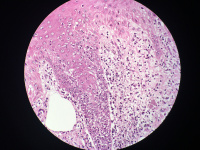

女性,鼻背部肿物3年,活检直径0.5厘米,

• 图1

考虑皮肤鲍温病

刺激性脂溢性角化病

高分化鳞癌

考虑鲍温氏病。

反转性毛囊角化病

激惹型脂溢性角化病。

日光性角化病